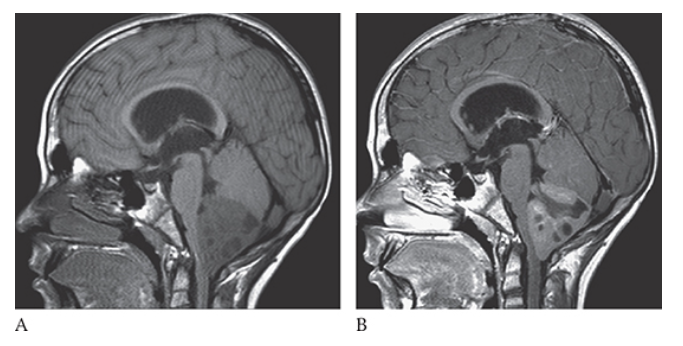

What is A

Medulloblastoma. Sagittal T1W image shows a large low-signal fourth ventricular mass with multiple cystic areas. The solid component enhances with gadolinium

What is B

Medulloblastoma. Sagittal T1W image Also note the hydrocephalus due to obstruction of CSF flow.